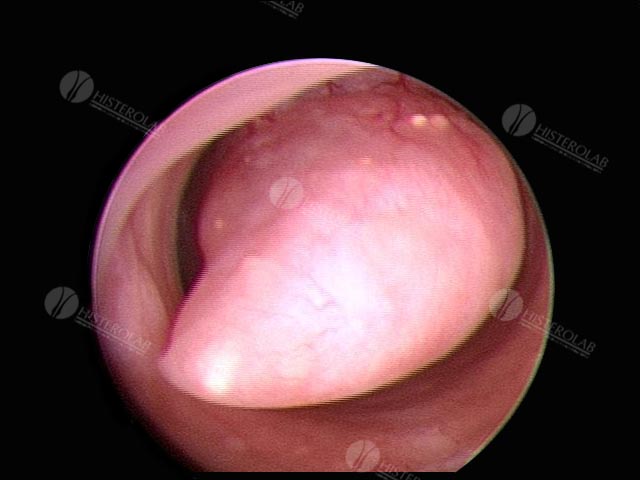

PÓLIPO ENDOMETRIAL

Os pólipos endometriais são uma das causas mais frequentes de sangramentos anormais tanto na pré como na pós-menopausa. No entanto, a maioria dos pólipos endometriais pode permanecer sem nenhum outro sintoma, sendo encontrados em exames ultrassonográficos realizados por outras causas. Eles se constituem de um crescimento anormal das glândulas endometriais e do estroma, formando uma projeção (um pólipo) na superfície interna do útero.

A maioria dos pólipos endometriais é benigna, mas pode ocorrer malignidade em algumas mulheres, por isso o diagnóstico preciso é importante.

Nos casos em que o exame mostra suspeita de malignidade a histeroscopia com biópsia é fundamental e permitirá o diagnóstico de certeza. Aproximadamente 95% dos pólipos endometriais são benignos. Como foi dito, alguns pólipos podem representar apenas hiperplasia endometrial ou miomas pedunculados com crescimento intrauterino.